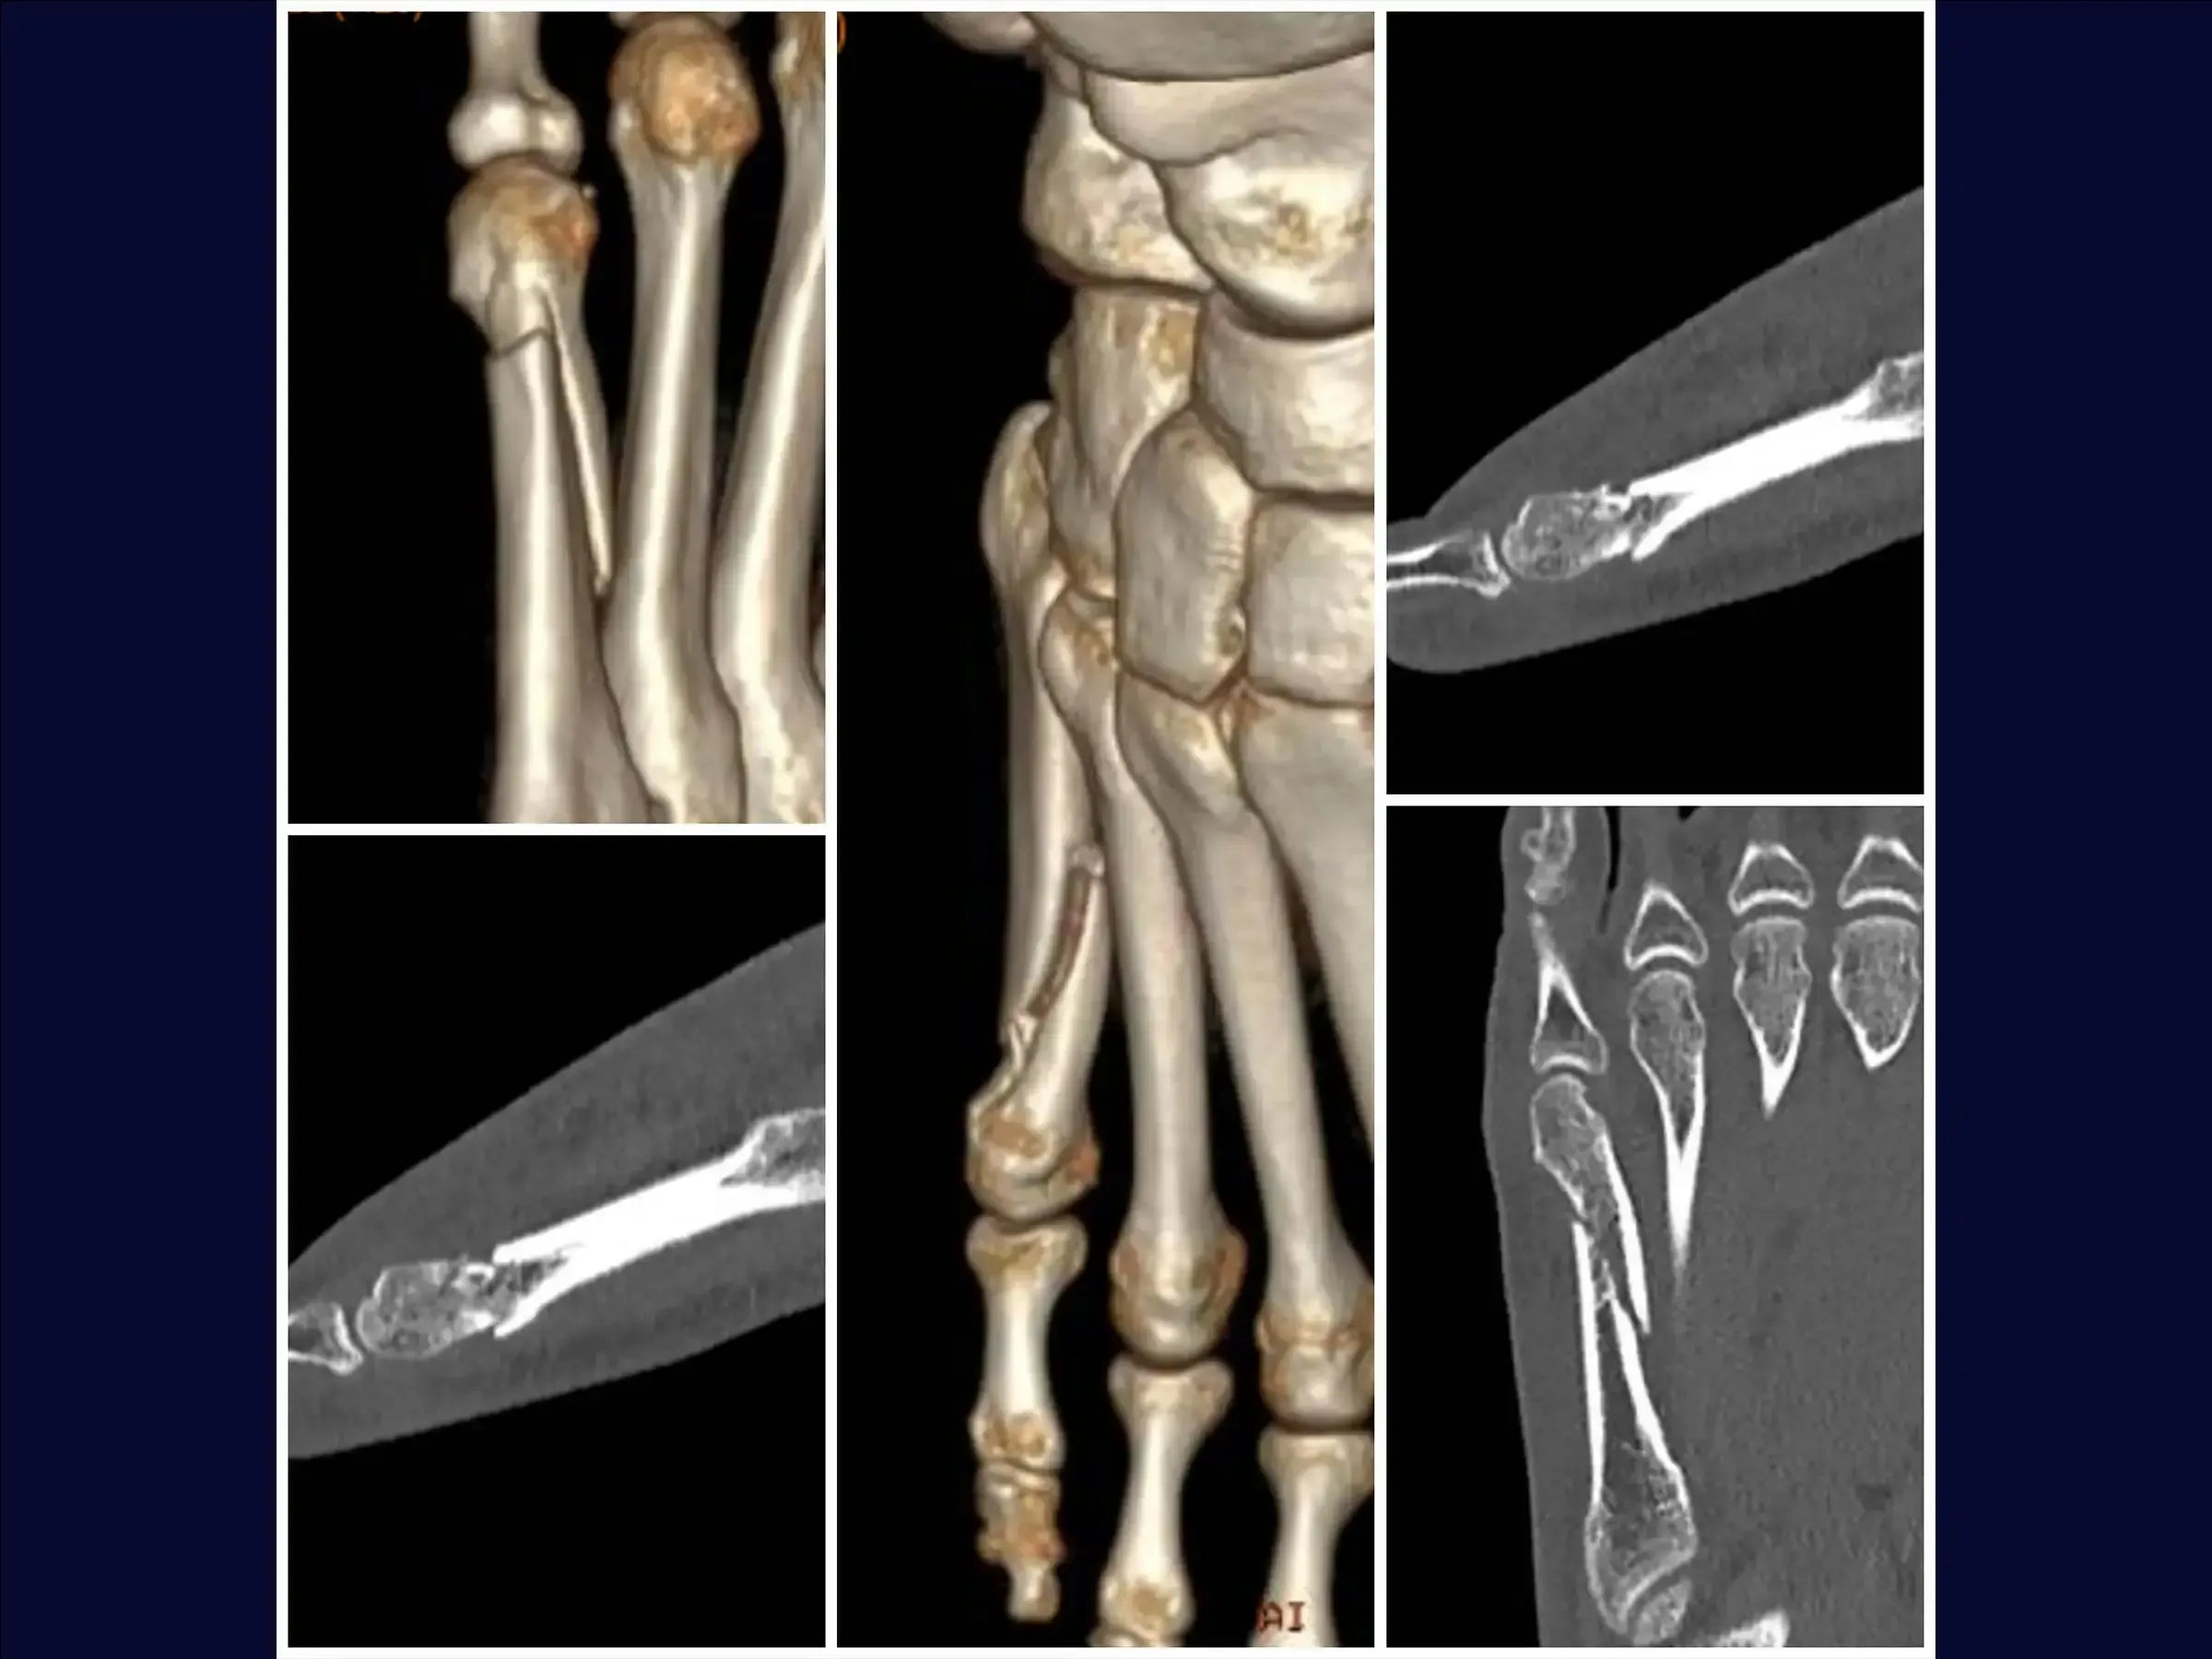

Mejore sus habilidades en el tratamiento quirúrgico de fracturas desplazadas del quinto metatarsiano. Este procedimiento requiere una reducción anatómica cuidadosa para evitar la metatarsalgia o la disfunción de la marcha, especialmente en pacientes jóvenes y atletas. Esta capacitación detalla el procedimiento quirúrgico con placa de bloqueo y tornillos, con énfasis en la rápida recuperación funcional y el retorno a la actividad deportiva.

- Evaluación y planificación del acceso: análisis de radiografías para identificar la angulación de la fractura y la posibilidad de alteración de la carga de peso, metatarsalgia o disfunción de la marcha.

- Reducción de la fractura y estabilización provisional: Identificación de los vértices de la fractura, reducción bajo visualización directa con pinza de reducción y estabilización provisional con agujas de Kirschner, evitando la zona de la futura placa.